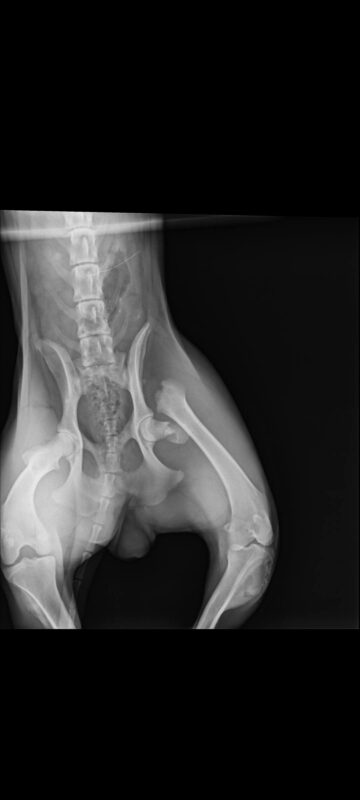

Η σημερινή επίσκεψη στην Κτηνίατρο Vasilia Ziogou έγινε χάρις την αγαπημένη μας Νεράιδα Katerina Papapostolou και το Ζω.ες που κάλυψε τα πρώτα έξοδα… Η Κατερίνα μας, γράφει μέρα νύχτα τα υπέροχα βιβλία της προκειμένου να βοηθήσει κάθε πονεμένο πλάσμα που βρίσκεται στον δρόμο της…Οι ακτινογραφίες έδειξαν αποκοπή της κεφαλής του μοιραίου οστού στο αριστερό πόδι. Για να σταθεί ξανά στα πόδια της είναι απαραίτητο το χειρουργείο. Είμαστε σε επαφή με κτηνιάτρους ώστε να μάθουμε το κόστος της επέμβασης…Το κορίτσι μας απολαμβάνει την βόλτα της με το αυτοκίνητο προς το παρόν κι εμείς βασιζόμαστε στην βοήθεια όλων σας…